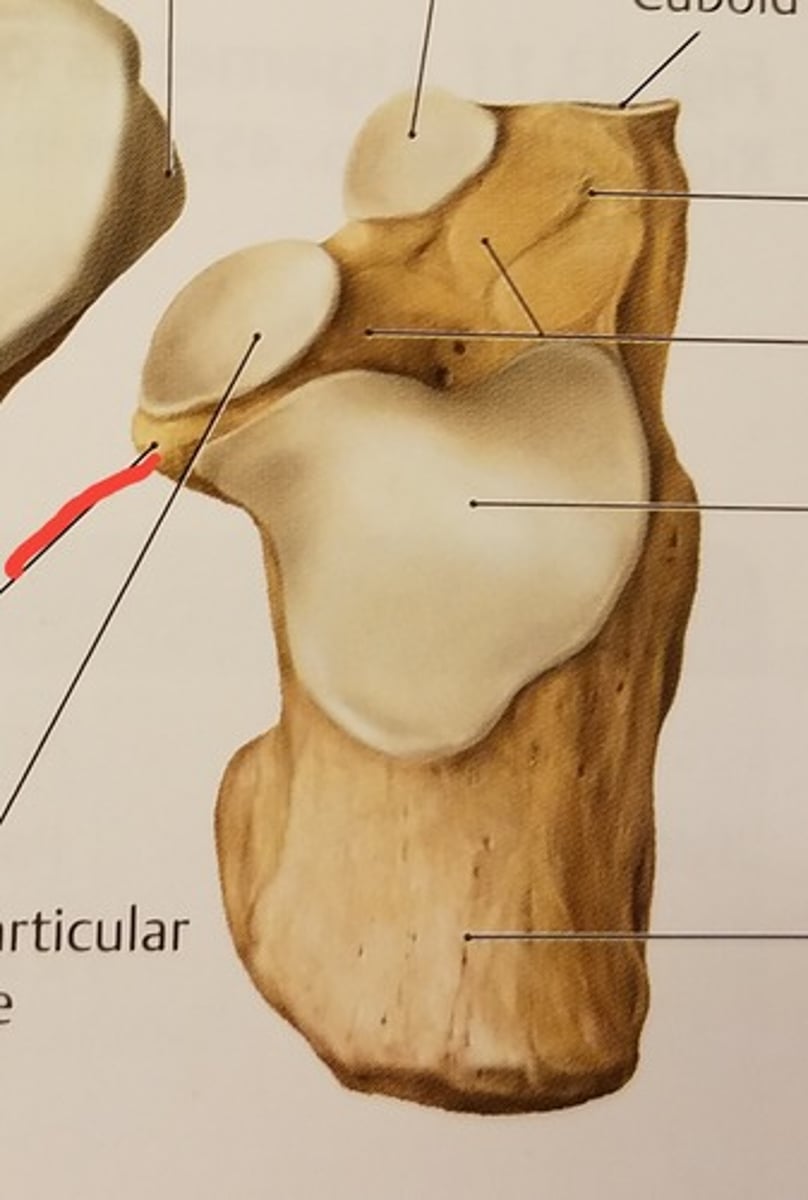

Calcaneus

Sustentaculum tali (medial shelf for talus)

Posterior talar articular surface

Middle talar articular surface

Anterior talar articular surface

Articular surface for cuboid bone

Tarsal sinus (sinus between talus and calcaneus)

Navicular

Cuboid bone